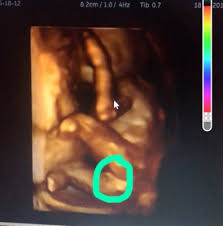

Dr Nabielek Ultraschallbilder 3d Ultraschall

Dr Nabielek Ultraschallbilder 3d Ultraschall from le-cdn.website-editor.net